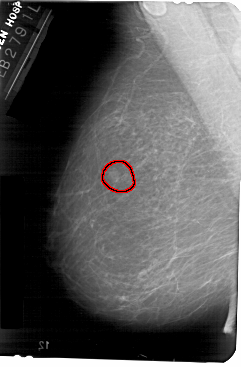

FILE: A_1375_1.LEFT_MLO.OVERLAY

TOTAL_ABNORMALITIES 1

ABNORMALITY 1

LESION_TYPE MASS SHAPE OVAL MARGINS ILL_DEFINED

ASSESSMENT 4

SUBTLETY 4

PATHOLOGY BENIGN

TOTAL_OUTLINES 1

BOUNDARY